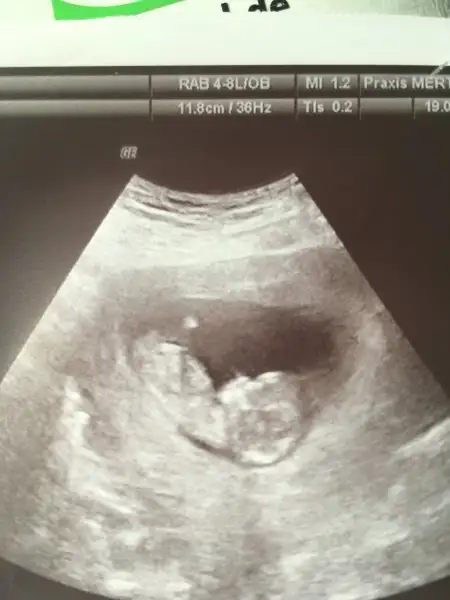

Masallah canimmm yarin da benim kontrol var darisi başıma insallahhhEki Görüntüle 2023119 Biz kontrolden geldik şükür herşey yolunda dedi doktorumuz, bebişimiz uyuyordu doktor rahatsız etmek istemedi.. haftaya ikili taramada cinsiyeti öğrenirsiniz dedi ama bakalım kısmet..

Eki Görüntüle 2023119 Biz kontrolden geldik şükür herşey yolunda dedi doktorumuz, bebişimiz uyuyordu doktor rahatsız etmek istemedi.. haftaya ikili taramada cinsiyeti öğrenirsiniz dedi ama bakalım kısmet..